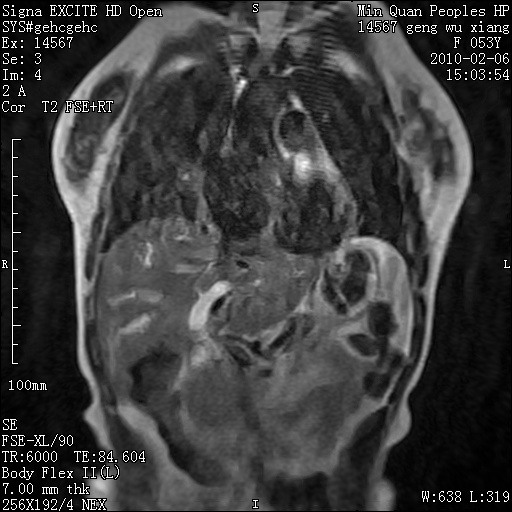

标题: MRI2762:胆道梗阻原因?

f,53y,全身黄染多日。

高位胆道梗阻 胆管癌可能性大

支持 高位胆道梗阻 胆管癌可能性大。